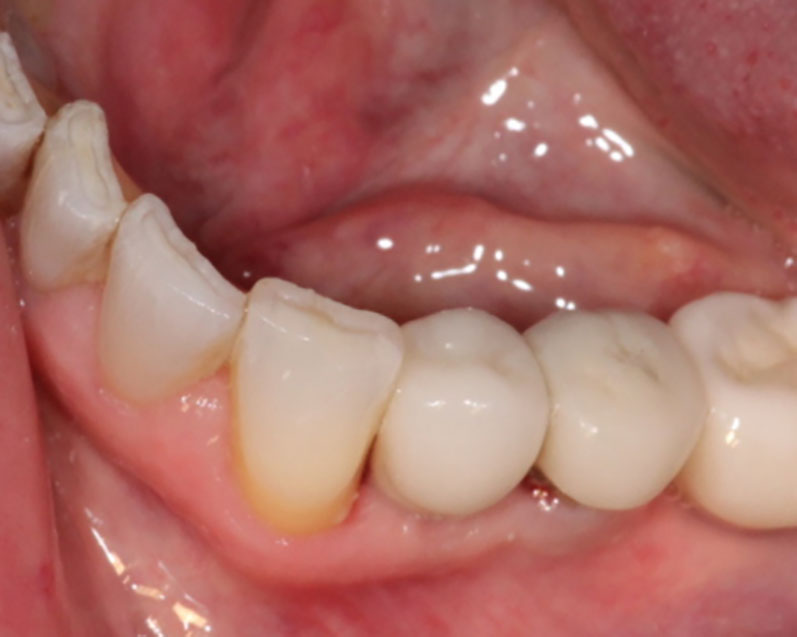

Implants

This treatment involves implanting artificial dental roots, and restoring dental crown without damaging the adjacent teeth.